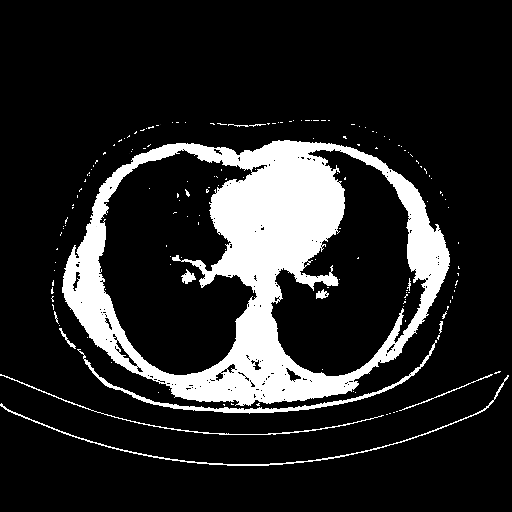

Slice 70 Targeting Evaluation

Patient ID: BM26032018

Model: cytran

Slice: Slice_70

Slice Thickness: 2.0mm

Conversion: NATIVE β VENOUS

4Γ3 grid: Rows show different image types (Original NATIVE, Reconstructed NATIVE, Original VENOUS, Generated VENOUS), Columns show windowing techniques (No Window, Lung Window, Mediastinum Window)